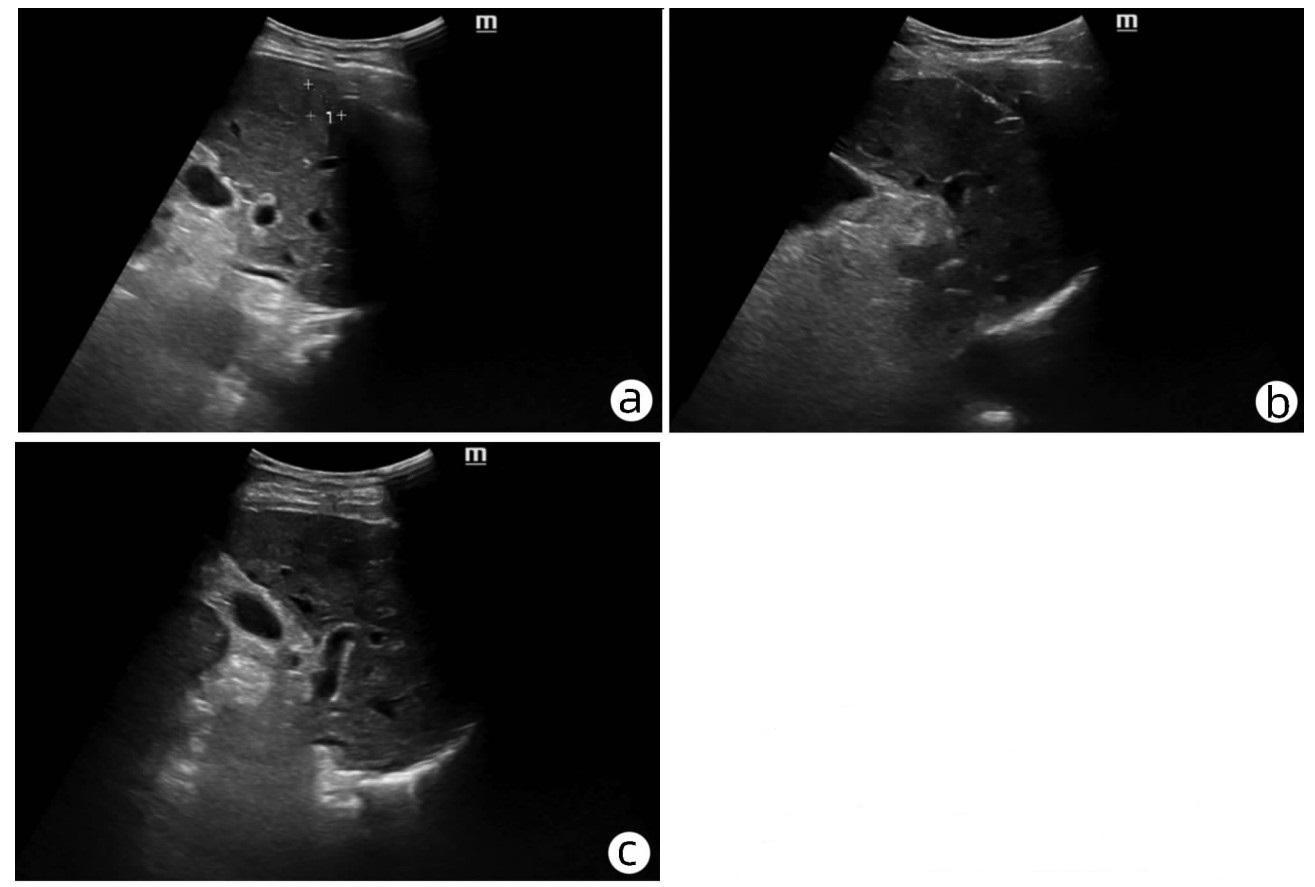

目的  通过回顾性分析肿瘤相关性急性胰腺炎(AP)患者的临床资料,评估胆胰及壶腹部肿瘤与AP发病之间的关系,探讨肿瘤相关性AP的临床特点。  方法  收集2013年1月—2021年8月郑州大学第一附属医院收治的AP患者病例资料。分析AP病因构成及肿瘤相关AP的发病率变化;对比分析肿瘤及非肿瘤AP,以及不同肿瘤部位AP的临床特征差异,探讨肿瘤相关AP的发病特点。正态分布的计量资料两组间比较采用t检验,多组间比较采用单因素方差分析,进一步两两比较采用SNK-q检验;非正态分布的计量资料两组间比较采用Mann-Whitney U检验,多组间比较采用Kruskal-Wallis H检验,进一步两两比较采用Wilcoxon秩和检验;计数资料二分类组间采用χ2检验或Fisher’s精确检验法比较,多分类组间比较采用拟合优度检验。应用受试者工作特征曲线(ROC曲线)评估胰腺肿瘤相关AP的鉴别因素;采用logistic多因素回归分析肿瘤相关性AP的独立影响因素。  结果  共入组AP患者8106例,肿瘤相关性AP患者84例,占1.04%。84例肿瘤相关AP患者平均年龄显著大于非肿瘤组(t=6.050, P<0.001)。初发AP至确诊肿瘤平均时间为7.38个月;轻症急性胰腺炎(MAP)75例(89.2%),中度重症急性胰腺炎(MSAP)8例(9.5%), 重症急性胰腺炎(SAP)1例(1.2%)。肿瘤来源于胆道下段11例(13.1%),壶腹部13例(15.5%),胰腺60例(71.4%)。AP反复发作(RR=8.362, 95%CI: 3.162~22.115)、胰管扩张(RR=10.996, 95%CI: 3.871~31.236)、胆管扩张(RR=7.738, 95%CI: 2.521~23.752) 和白细胞计数(RR=0.766, 95%CI: 0.666~0.881)是肿瘤相关性AP的独立影响因素(P值均<0.001)。  结论  肿瘤相关AP以中老年男性多发,临床多表现为MAP、易反复,多伴胰胆管扩张,肿瘤标志物CA19-9持续性升高等。具有上述特征且无明显诱因的AP需完善胆胰及壶腹部的影像学精查,并加强随访,避免肿瘤漏诊影响预后。